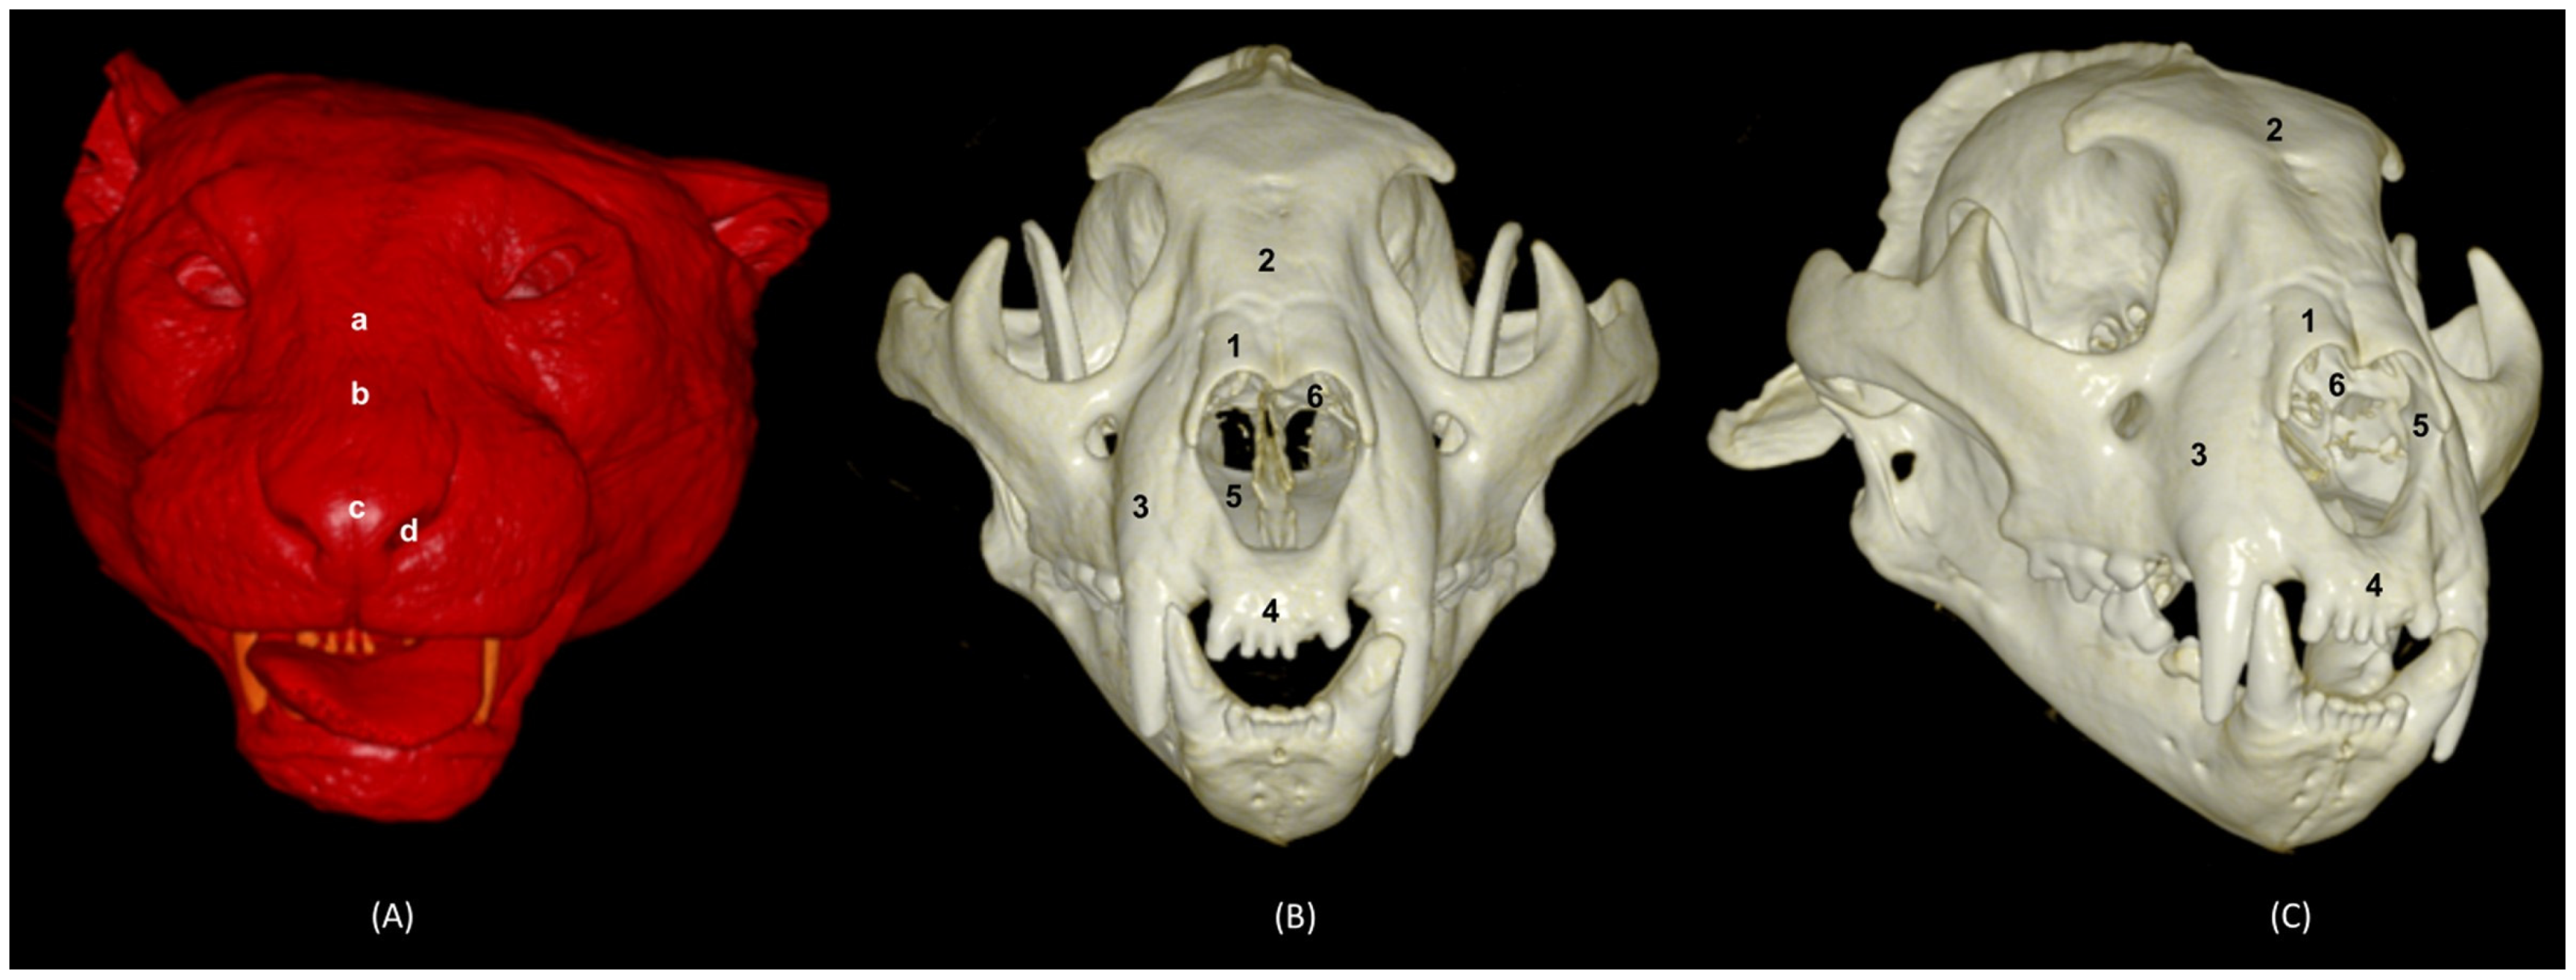

In addition, four OsiriX surface and deep VR reconstruction CT images of the felid’s heads are presented (Figure 31, Figure 32, Figure 33 and Figure 34). These VR images allowed for the assessment of the external nose and the integrity and the extensions of the bones, enhancing the anatomical understanding of this region.

In the lion CT VR images (Figure 32), we could also observe the external nose and these bones. However, the morphology of these skulls differed from the rest. The short rostral extension of the nasal bone was observed, as well as the convex morphology that the frontal bone acquires. The bone structure was much more compact than in other felines.

Figure 32. OsiriX 3D reconstructed CT images of the lion’s head showing the external nares and nasal plane. (A): VR surface reconstruction. Rostral view. (B): VR deep reconstruction. Rostral view. (C) VR deep reconstruction. Right rostrolateral view. a. Root of the nose; b. Dorsum of the nose; c. Tip of the nose; d. Nasal orifice; 1. Nasal bone; 2. Frontal bone; 3. Maxilla; 4. Incisive bone; 5. Nasal cavity; 6. Turbinates.

In the reconstruction of the cheetah’s head (Figure 33), the limit between the frontal and nasal bones was not so pronounced. The frontal bone in the cheetah was completely concave, unlike the lion.

Figure 33. OsiriX 3D reconstructed CT images of the cheetah’s head showing the external nares and nasal plane. (A): VR surface reconstruction. Rostral view. (B): VR deep reconstruction. Rostral view. (C) VR deep reconstruction. Right rostrolateral view. a. Root of the nose; b. Dorsum of the nose; c. Tip of the nose; d. Nasal orifice; 1. Nasal bone; 2. Frontal bone; 3. Maxilla; 4. Incisive bone; 5. Nasal cavity; 6. Turbinates.

Finally, the VR reconstruction of the domestic cat skull (Figure 34) showed that the bone limits were not as noticeable as in the leopard or cheetah. The frontal bone represents a large extension since its zygomatic process developed very laterally, unlike in big felids.

Figure 34. OsiriX 3D reconstructed CT images of the cat’s head showing the external nares and nasal plane. (A): VR surface reconstruction. Rostral view. (B): VR deep reconstruction. Rostral view. (C) VR deep reconstruction. Right rostrolateral view. a. Root of the nose; b. Dorsum of the nose; c. Tip of the nose; d. Nasal orifice; 1. Nasal bone; 2. Frontal bone; 3. Maxilla; 4. Incisive bone; 5. Nasal cavity; 6. Turbinates.